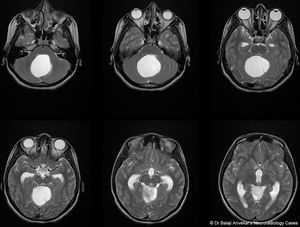

Pilocytic astrocytoma is a brain tumor that occurs more often in children and young adults (in the first 20 years of life). They usually arise in the cerebellum, near the brainstem, in the hypothalamic region, or the optic chiasm, but they may occur in any area where astrocytes are present, including the cerebral hemispheres and the spinal cord. These tumors are usually slow growing and benign.[1] The neoplasms are associated with the formation of a single (or multiple) cyst(s), and can become very large. Children affected by pilocytic astrocytoma can present with different symptoms that might include failure to thrive (lack of appropriate weight gain), headache, nausea, vomiting, irritability, torticollis (tilt neck or wry neck) difficulty to coordinate movements and visual complaints (including nystagmus).